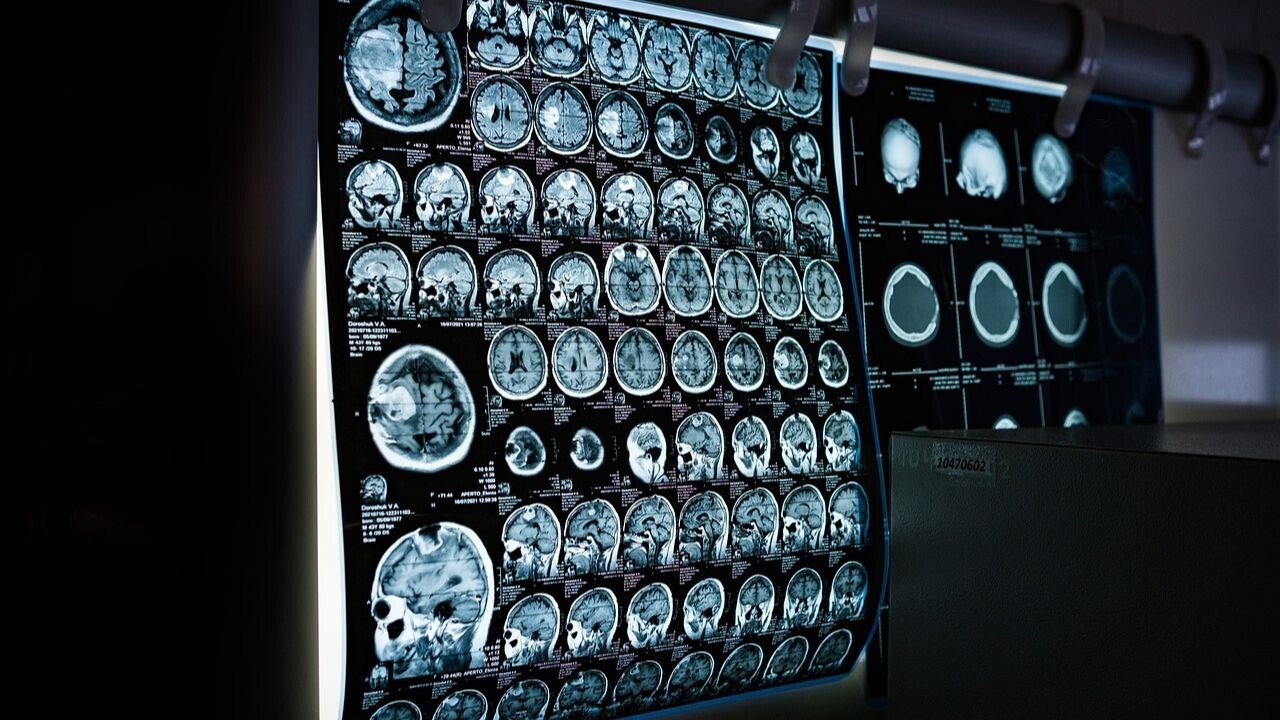

A new VR system that uses eye-tracking technology can calm children while they undergo Magnetic Resonance Imaging (MRI) scanning.

Developed by researchers at King’s College London, the method aims to mitigate children’s tendency to move during MRI scans. by engaging them in immersive virtual reality experiences.

Compared to adults, children are less likely to remain still inside the scanner, often negatively influenced by the large size of the machine and the loud noises. As movement can disrupt the quality of the images, doctors frequently have to resort to approaches such as sedation or general anaesthesia.